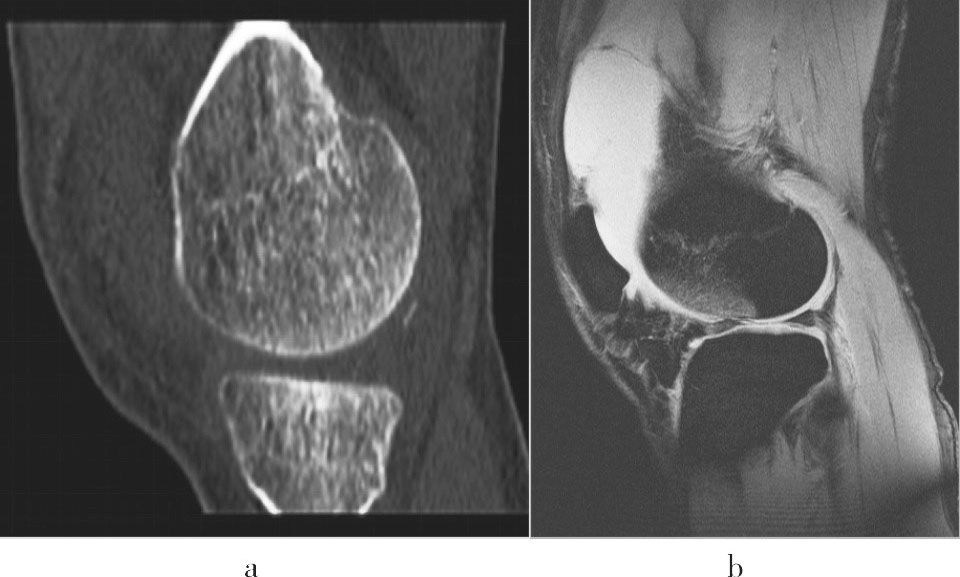

图1-14 MRI与CT图像的区别

a.CT 图像,对骨的细节显示清晰,但周围软组织显示不良;b.MRI 图像,各种性质的软组织有明显信号差异,但骨的细节显示不如CT。

正因为MRI 与CT 的原理不同,它们的适用范围也有不同。如高密度的骨骼和低密度含气的肺在CT 图像上由于密度对比好就显示得非常清晰,但由于它们的质子密度很低,MRI 信号也就不高,反而难以显示。对于软组织病变,由于密度差异不大,CT的显示有些无能为力,而MRI 则可以通过设置不同的扫描参数,形成非常丰富的信号差异,从而得到良好显示(图1-14)。

对比了MRI 与CT 的不同以后,MRI 的优势也就明朗了。这就是没有辐射危害,软组织分辨力特别高。所以,对于孕妇和婴幼儿这些对射线敏感的人群,就应该优选MRI 检查;而对于观察脑、脊髓、肌腱、韧带、软骨及关节内结构等软组织来说,选用MRI 也有极大的优势。